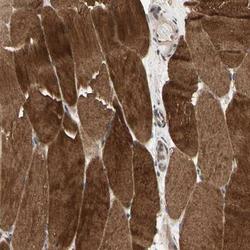

- Main image

- Experimental details

- Immunohistochemistry-Paraffin: MLK2 Antibody [NBP1-87737] - Staining of human skeletal muscle shows strong cytoplasmic positivity in myocytes.